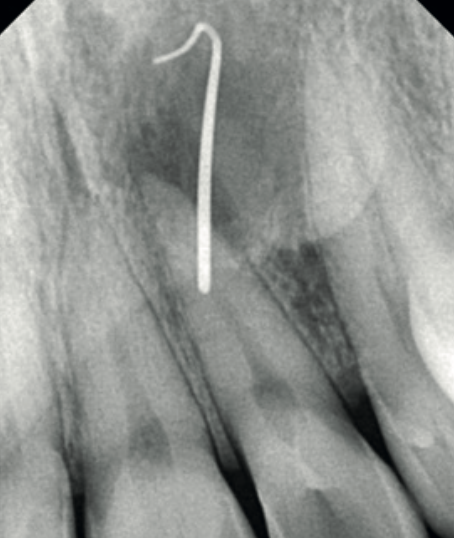

A periapical radiograph of the upper left lateral incisor (UL2) was taken with sinus tracing through the palatal swelling. It was inconclusive. The 2D image could not establish a diagnosis. The referring clinician was stuck.

Clinical photograph of palatal swelling adjacent to the upper left lateral incisor Periapical radiograph of UL2 with sinus tracing — inconclusive for aetiology

Fig. 1 & 2 Left: clinical photograph showing the palatal swelling. Right: periapical radiograph of UL2 with sinus tracing — inconclusive. No obvious caries, restorations, or trauma visible.